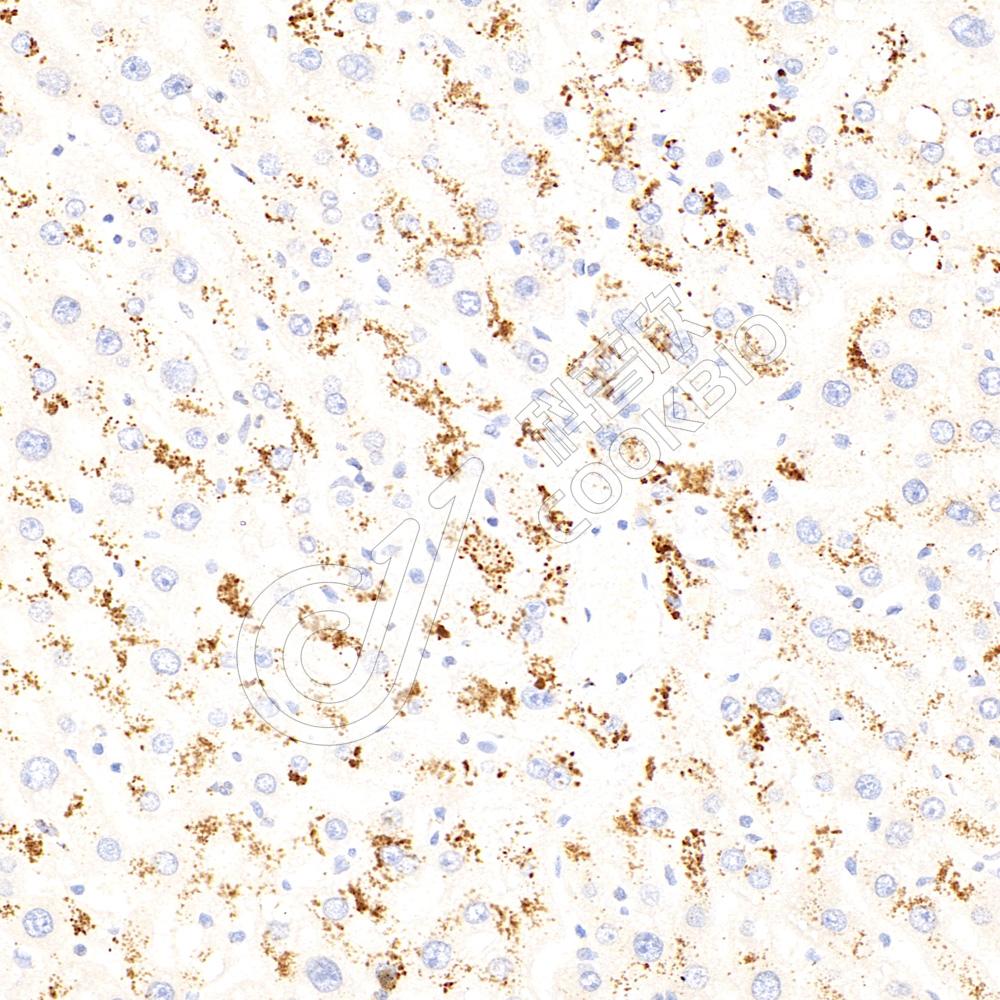

IHC检测CBS蛋白(货号 K1335382).

样品: 小鼠脑, 4%多聚甲醛 (货号KSG1101) 固定12-24小时.

抗原修复: 柠檬酸抗原修复液(干粉, pH 6.0) (KSG1201), 98℃, 20分钟.

—抗: 1: 500稀释, 4℃ 孵育过夜.

二抗: S-vision免疫组化多聚二抗(山羊抗兔),即用型 (货号KB3906), 室温孵育20分钟.